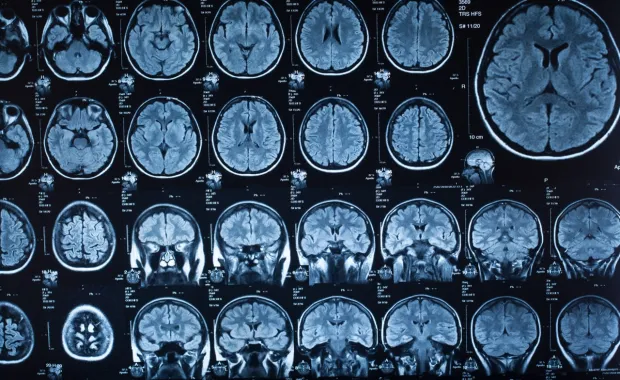

The AI Head Analysis solution uses AI to analyze CT head scans as part of real-time emergency treatment to support the diagnosis of five types of acute brain bleeds.

This globally groundbreaking AI solution identifies the most common non-trauma-induced brain bleeds to assist on-call physicians in interpreting CT images of the head. The solution’s AI algorithms:

• Detect anomalies and identify in real time CT scans that call for urgent attention

• Identify the most common types of brain bleeds, covering >99% of acute brain bleeds

• Identify a specific brain bleed with 98% accuracy